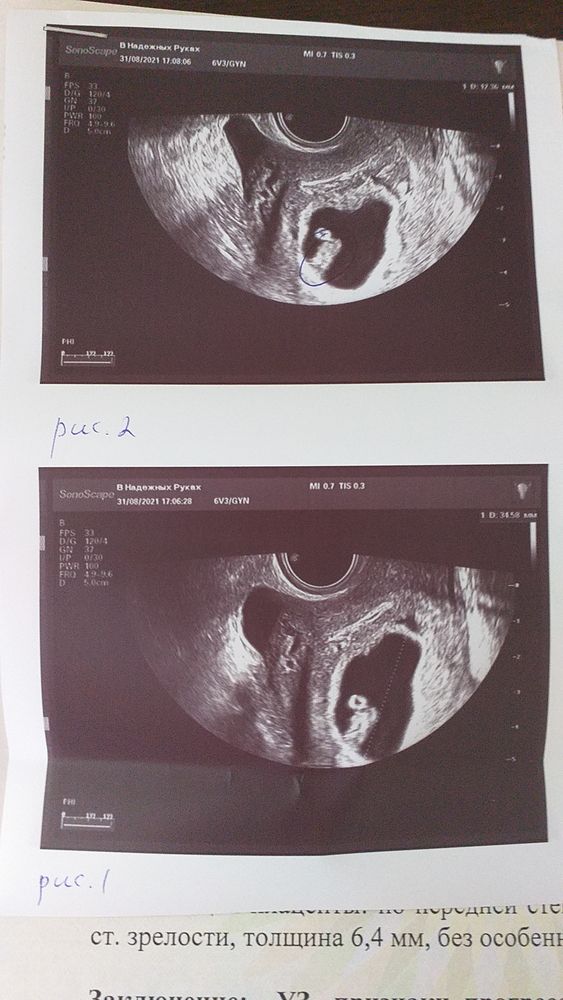

Всё о нашей беременностиСходила на повторное узи. Акушерский срок 8 недель и 4 дня, эмбриональный 6 нед 4 дня. Срок поставили 7-8 эмбриональных недель. Пошли уже на перегон (2 недели назад еще отставали)

ПЯ 34,6 мм

КТР 12,3 мм

ЖМ 3,4 мм

Амион до 14,3 мм

СБ определяется

ПЯ по задней стенке. Плацента по передней. Толщина 6,4 мм

Гипертонус миометрия.